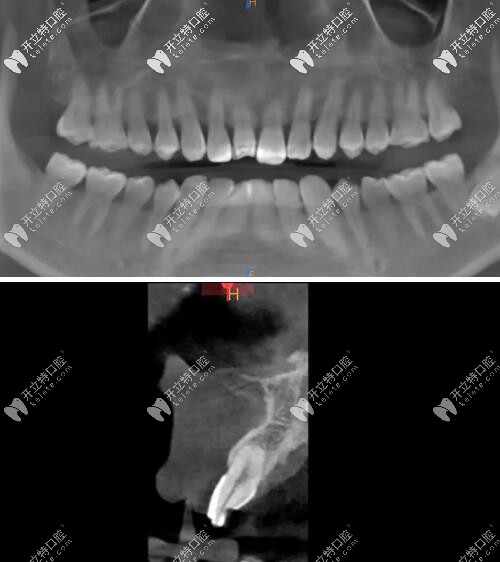

術(shù)后CBCT顯示植入正確的三維位置,種植體唇側(cè)骨量充足;

瑞士iti鈦親水BL 4.1mm*10mm種植體